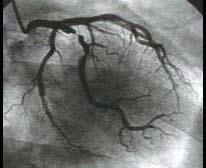

问题 图中冠状动脉造影结果为 ( )

选项 A、右冠近端99%狭窄 B、左冠前降支近端99%狭窄 C、右冠远端99%狭窄 D、中间支近端99%狭窄 E、左主干近端99%狭窄

答案 D